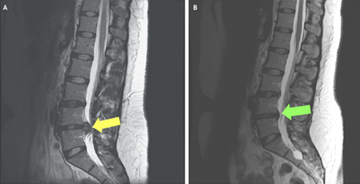

A microdiscectomy is a minimally invasive spinal surgery designed to relieve symptoms caused by a herniated or damaged disc. In this procedure, the surgeon removes the small portion of disc material that is pressing on a nearby nerve root, helping to reduce pain, numbness, or weakness in the back, legs, or arms. Unlike a traditional open discectomy, a microdiscectomy uses a much smaller incision and specialised instruments, often with the assistance of a surgical microscope. This approach minimises disruption to surrounding muscles and tissues, which can lead to faster recovery and less post-operative discomfort.

• Herniated Disc: Protrusion of disc material that compresses spinal nerves.